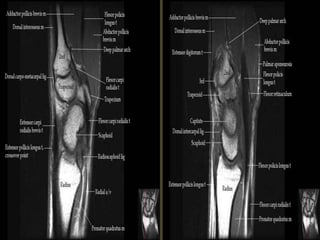

The transverse carpal ligament (short arrows) extends from the hook of the hamate (long

arrow) to the tubercle of the trapezium (arrowhead), forming the floor of the carpal tunnel.

At the radial aspect of the carpal tunnel, the flexor digitorum tendons are arranged in two

rows (separated by dotted line), the profundus tendons deep to the superficialis tendons. The

flexor pollicis longus tendon (star) is positioned at the ulnar aspect of the tunnel, separated

from the flexor carpi radialis tendon (curved arrow) by a ligamentous reflection of the

transverse carpal ligament. The median nerve is indicated (asterisk). - See more at:

http://radsource.us/palmar-bursae-and-flexor-tendon-sheaths/#sthash.mSFX1u0c.dpuf